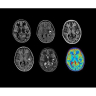

• ImageWorks — повысит производительность МРТ благодаря визуализации высокого качества с MAGIC, четкими результатами пост-процессинга с READYView.